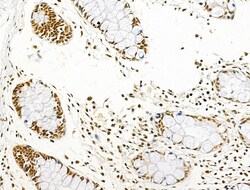

| Immunohistochemistry (Paraffin), Western Blot, Immunocytochemistry | |

| A synthesized peptide derived from human AKT1(Accession P31749), corresponding to amino acid residues around phosphorylated Ser124. | |

| Human, Mouse, Rat | |